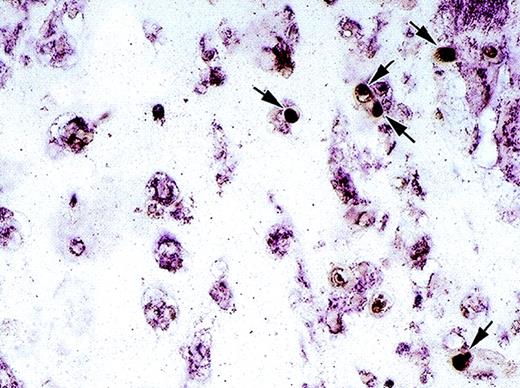

We wished to confirm these results and looked for the presence of IP-10 protein by immunohistochemistry (Fig 6, see page 1616). Using an antiserum to murine IP-10, essentially no immunopositive cells were detected in Matrigel plugs alone (Fig 6A), Matrigel plugs induced by bFGF (Fig 6B), or Matrigel plugs induced by bFGF in mice treated with anti–NK 1.1 antibody (Fig6D). By contrast, strong positive staining was detected in Matrigel plugs impregnated with bFGF and IL-12, mostly localized at the periphery of the plug (Fig 6C). Since most of the cells in these plugs were identified as endothelial cells due to their staining for von Willebrand factor (Fig 2), we concluded that endothelial cells infiltrating the plugs are a likely source of IP-10 in the presence of IL-12. After treatment with anti–NK 1.1 antibody, Matrigel plugs impregnated with bFGF and IL-12 displayed occasional IP-10 faintly immunopositive cells (Fig 6E). These results are consistent with those from RT-PCR analysis, and demonstrate the presence of IP-10 at those sites where angiogenesis is inhibited by IL-12.

Immunohistochemical detection of murine IP-10 in Matrigel plugs from C57BL/6 mice treated with or without anti–NK 1.1 monoclonal antibody treatment. Paraffin-embedded sections from Matrigel plugs alone (A); plugs impregnated with bFGF (B); plugs impregnated with bFGF + IL-12 (C); plugs impregnated with bFGF + monoclonal anti–NK 1.1 antibody (D); and plugs impregnated with bFGF + IL-12 + monoclonal anti–NK 1.1 antibody (E) were stained with a rabbit antimouse IP-10 antiserum and counterstained with hematoxylin. Some IP-10–positive cells (brown) are indicated by arrows. Original magnification ×40.